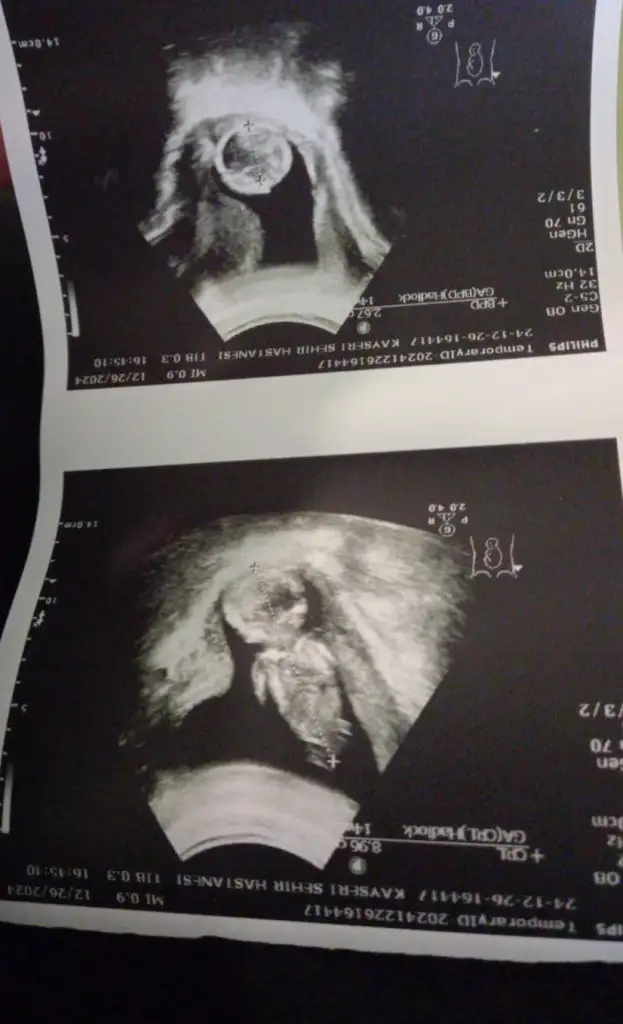

Merhaba benimkini de söyler misiniz? Karından, 14+4 haftalık